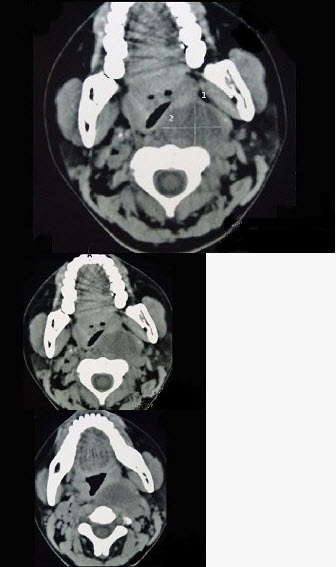

女性,34岁,自诉1个月前被咽喉部被鱼刺刺伤,近半个月发热,咽喉部疼痛,CT检查如图所示,请选择正确的描述和结论()。

A、左侧咽后壁可见低密度肿块影

B、肿块内密度均匀

C、考虑咽后壁脓肿

D、考虑神经源性肿瘤

E、考虑血管瘤

A,B,C